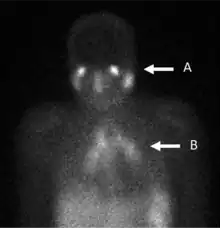

A gallium scan is a type of nuclear medicine test that uses either a gallium-67 (67Ga) or gallium-68 (68Ga) radiopharmaceutical to obtain images of a specific type of tissue, or disease state of tissue. Gallium salts like gallium citrate and gallium nitrate may be used. The form of salt is not important, since it is the freely dissolved gallium ion Ga3+ which is active.[1] Both 67Ga and 68Ga salts have similar uptake mechanisms.[2] Gallium can also be used in other forms, for example 68Ga-PSMA is used for cancer imaging. The gamma emission of gallium-67 is imaged by a gamma camera, while the positron emission of gallium-68 is imaged by positron emission tomography (PET).

Gallium salts are taken up by tumors, inflammation, and both acute and chronic infection,[3][4] allowing these pathological processes to be imaged. Gallium is particularly useful in imaging osteomyelitis that involves the spine, and in imaging older and chronic infections that may be the cause of a fever of unknown origin.[5][6]

In the past, the gallium scan was the gold standard for lymphoma staging, until it was replaced by positron emission tomography (PET) using fludeoxyglucose (FDG).[9][10] Gallium imaging is still used to image inflammation and chronic infections, and it still sometimes locates unsuspected tumors as it is taken up by many kinds of cancer cells in amounts that exceed those of normal tissues. Thus, an increased uptake of gallium-67 may indicate a new or old infection, an inflammatory focus from any cause, or a cancerous tumor.

In a normal scan, uptake of gallium is seen in wide range of locations which do not indicate a positive finding. These typically include soft tissues, liver, and bone. Other sites of localisation can be nasopharyngeal and lacrimal glands, breasts (particularly in lactation or pregnancy), normally healing wounds, kidneys, bladder and colon.[26]